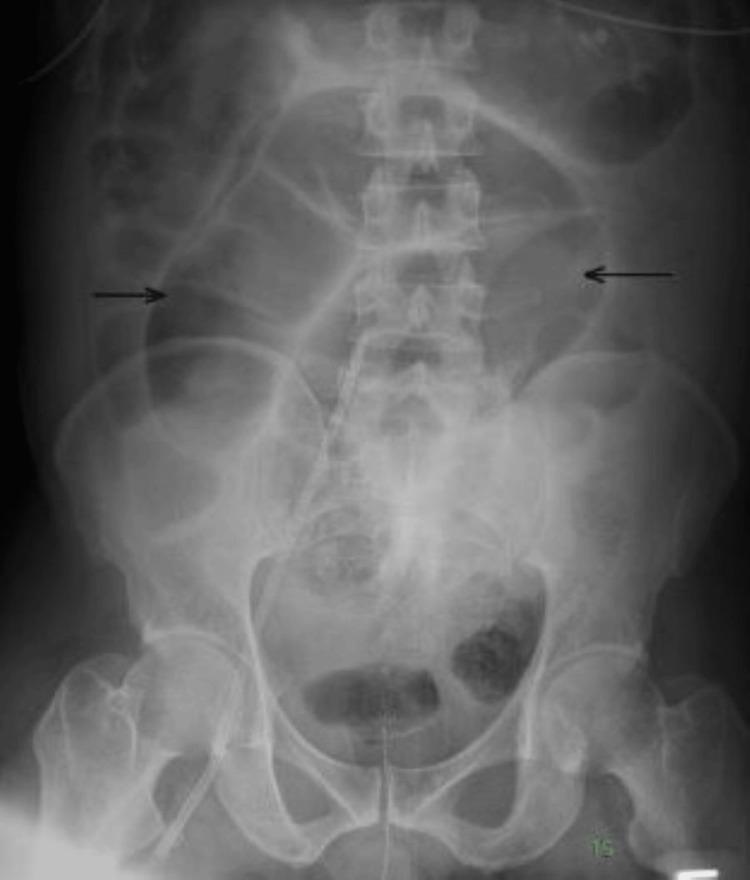

Sepsis is characterized by a dysregulated immune response to an infection. It is a major public health problem owing to its high mortality and morbidity. Sepsis is a medical emergency and requires aggressive and timely management. It can cause multiorgan failure, unmask an existing but undiagnosed disease such as ornithine transcarbamylase deficiency (OTCD), or make a known well-controlled disease worse. We present the case of a 52-year-old male who was brought to the emergency department unresponsive. He was diagnosed with severe sepsis which was associated with multiorgan failure and hyperammonemia crisis. Hyperammonemia was due to a newly diagnosed, late-onset OTCD which was unmasked by severe sepsis. This case will enable physicians to be aware and consider OTCD in a patient presenting with severe sepsis, altered mentation, and seizures, with no obvious cause of hyperammonemia.

脓毒症的特征是对感染的免疫反应失调。由于其高死亡率和高发病率,它是一个重大的公共卫生问题。脓毒症是一种医疗急症,需要积极及时的治疗。它可导致多器官功能衰竭,使现有的未被诊断的疾病(如鸟氨酸转氨甲酰酶缺乏症(OTCD))暴露,或使已知病情得到良好控制的疾病恶化。我们报告一例52岁男性患者,被送至急诊科时无反应。他被诊断为严重脓毒症,伴有多器官功能衰竭和高氨血症危象。高氨血症是由新诊断出的迟发性OTCD引起的,该疾病因严重脓毒症而暴露。该病例将使医生在遇到严重脓毒症、精神状态改变和癫痫发作且无明显高氨血症病因的患者时,能够意识到并考虑OTCD。